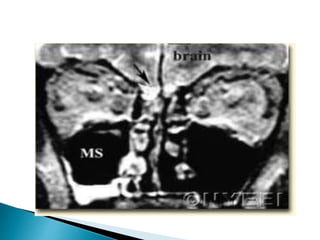

 Better forevaluating intracranial and intraorbital extension ◦ Evaluate for inflammatory change in orbital fat and extraocular muscles ◦ Obliteration of periantral fat is a subtle sign of extension ◦ Leptomeningeal enhancement progressing to cerebritis and abscess

Aspergillus involving thesphenoid sinus with invasion of the left cavernous sinus, thrombosis, extension to the left sylvian fissure and infratemporal fossa with cerebral infarctions.

• 21.

Aspergillus in leftmaxillary sinus with extension anterior and posterior to the retroantral space. There is diffuse involvement of the muscles of mastication.